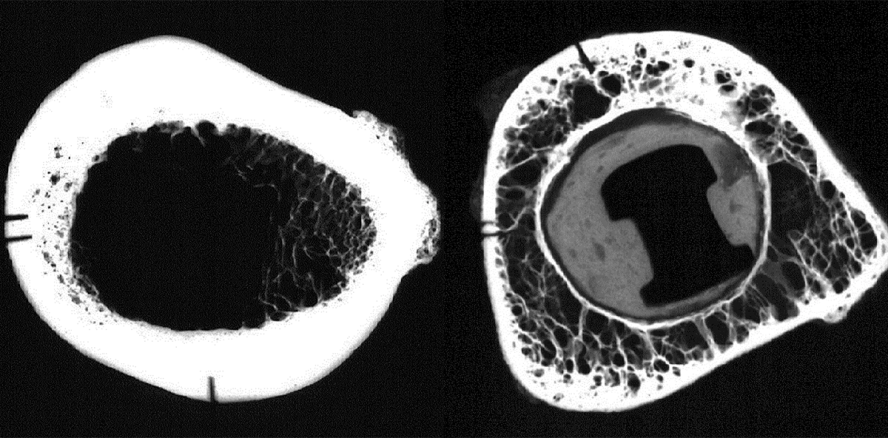

Histologische Untersuchungen zeigen: Osteonaler Knochen besteht aus langen röhrenartigen Strukturen, die sich weiträumig spiralig umeinander winden und einander durchdringen. In der Peripherie eines langen Knochens halten ringsum verlaufende Knochenlamellen periostalen Ursprungs dieses Kabelbündel zusammen. Die einzelnen Osteone sind von einer dünnen Schicht von nicht mineralisiertem Gewebe umgeben, d. h. gegeneinander sind sie nicht osseointegriert. Ein typischer Effekt, der Spannung auf den Knochen ausübt, ist ein „osteonales Herausziehen“ (osteonal pullout). Einzelne Osteonen werden aus einem Block anderer Osteonen (z. B. bei der Biegung des Knochens) herausgezogen.

Gleichermaßen können Schichten von Osteonen ins Gleiten geraten und gegenüber anderen Schichten verschoben werden. In diesem Fall lassen sich deutliche Gleitlinien (slip lines) innerhalb des Knochens feststellen. Wenn sich Knochen unter funktioneller Belastung verformt, verschieben sich Knochenschichten oder einzelne Osteonen gegeneinander. Wenn Implantate in diesem Knochen integriert sind, dann blockieren sie lokal eine Verschiebung und Verformung. Sie blockieren das Verschieben einzelner Osteonen und/oder das Verrutschen von Osteonenschichten. Folglich müssen andere Schichten mehr gleiten oder die gesamten Knochensegmente werden übermäßig starr. Im Vergleich zu Knochen ohne osseointegrierte Implantate verändert sich die Verteilung der Mineralisierung.

Neben dem internen Remodeling wird auch durch das periphere Modelling die Morphologie des Knochens verändert. Die äußere Form des Knochens ändert sich durch Modelling, wobei das Implantat in Arealen integriert bleibt, an denen Knochen verbleibt. Wie Abbildung 13 zeigt, kann der Knochen von allen Seiten durch Modelling resorbiert werden. Wenn er von oben nach unten wegmodelliert wird, werden wir leicht in Versuchung kommen, dies eine Periimplantitis zu nennen. Diese Bezeichnung ist falsch, weil sie die Ursache des Problems nicht widerspiegelt. Es stimmt allerdings, dass freiliegende raue Oberflächen des Implantats mit Bakterien besiedelt werden und dies eine Entzündung der periimplantären Weichgewebe zur Folge hat.